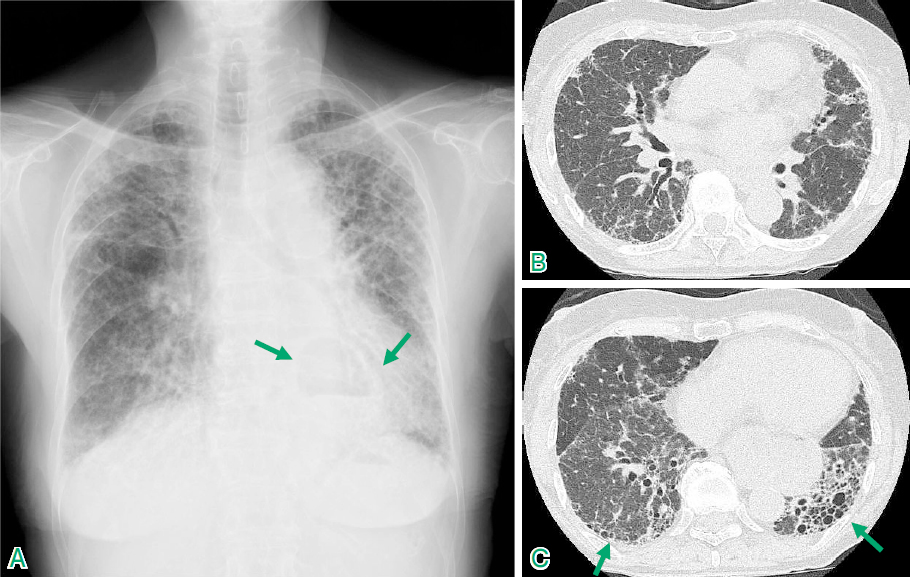

- 胸部X線検査:病気や進行の兆候を調べるため。

- CT スキャン:肺の瘢痕を調べます。